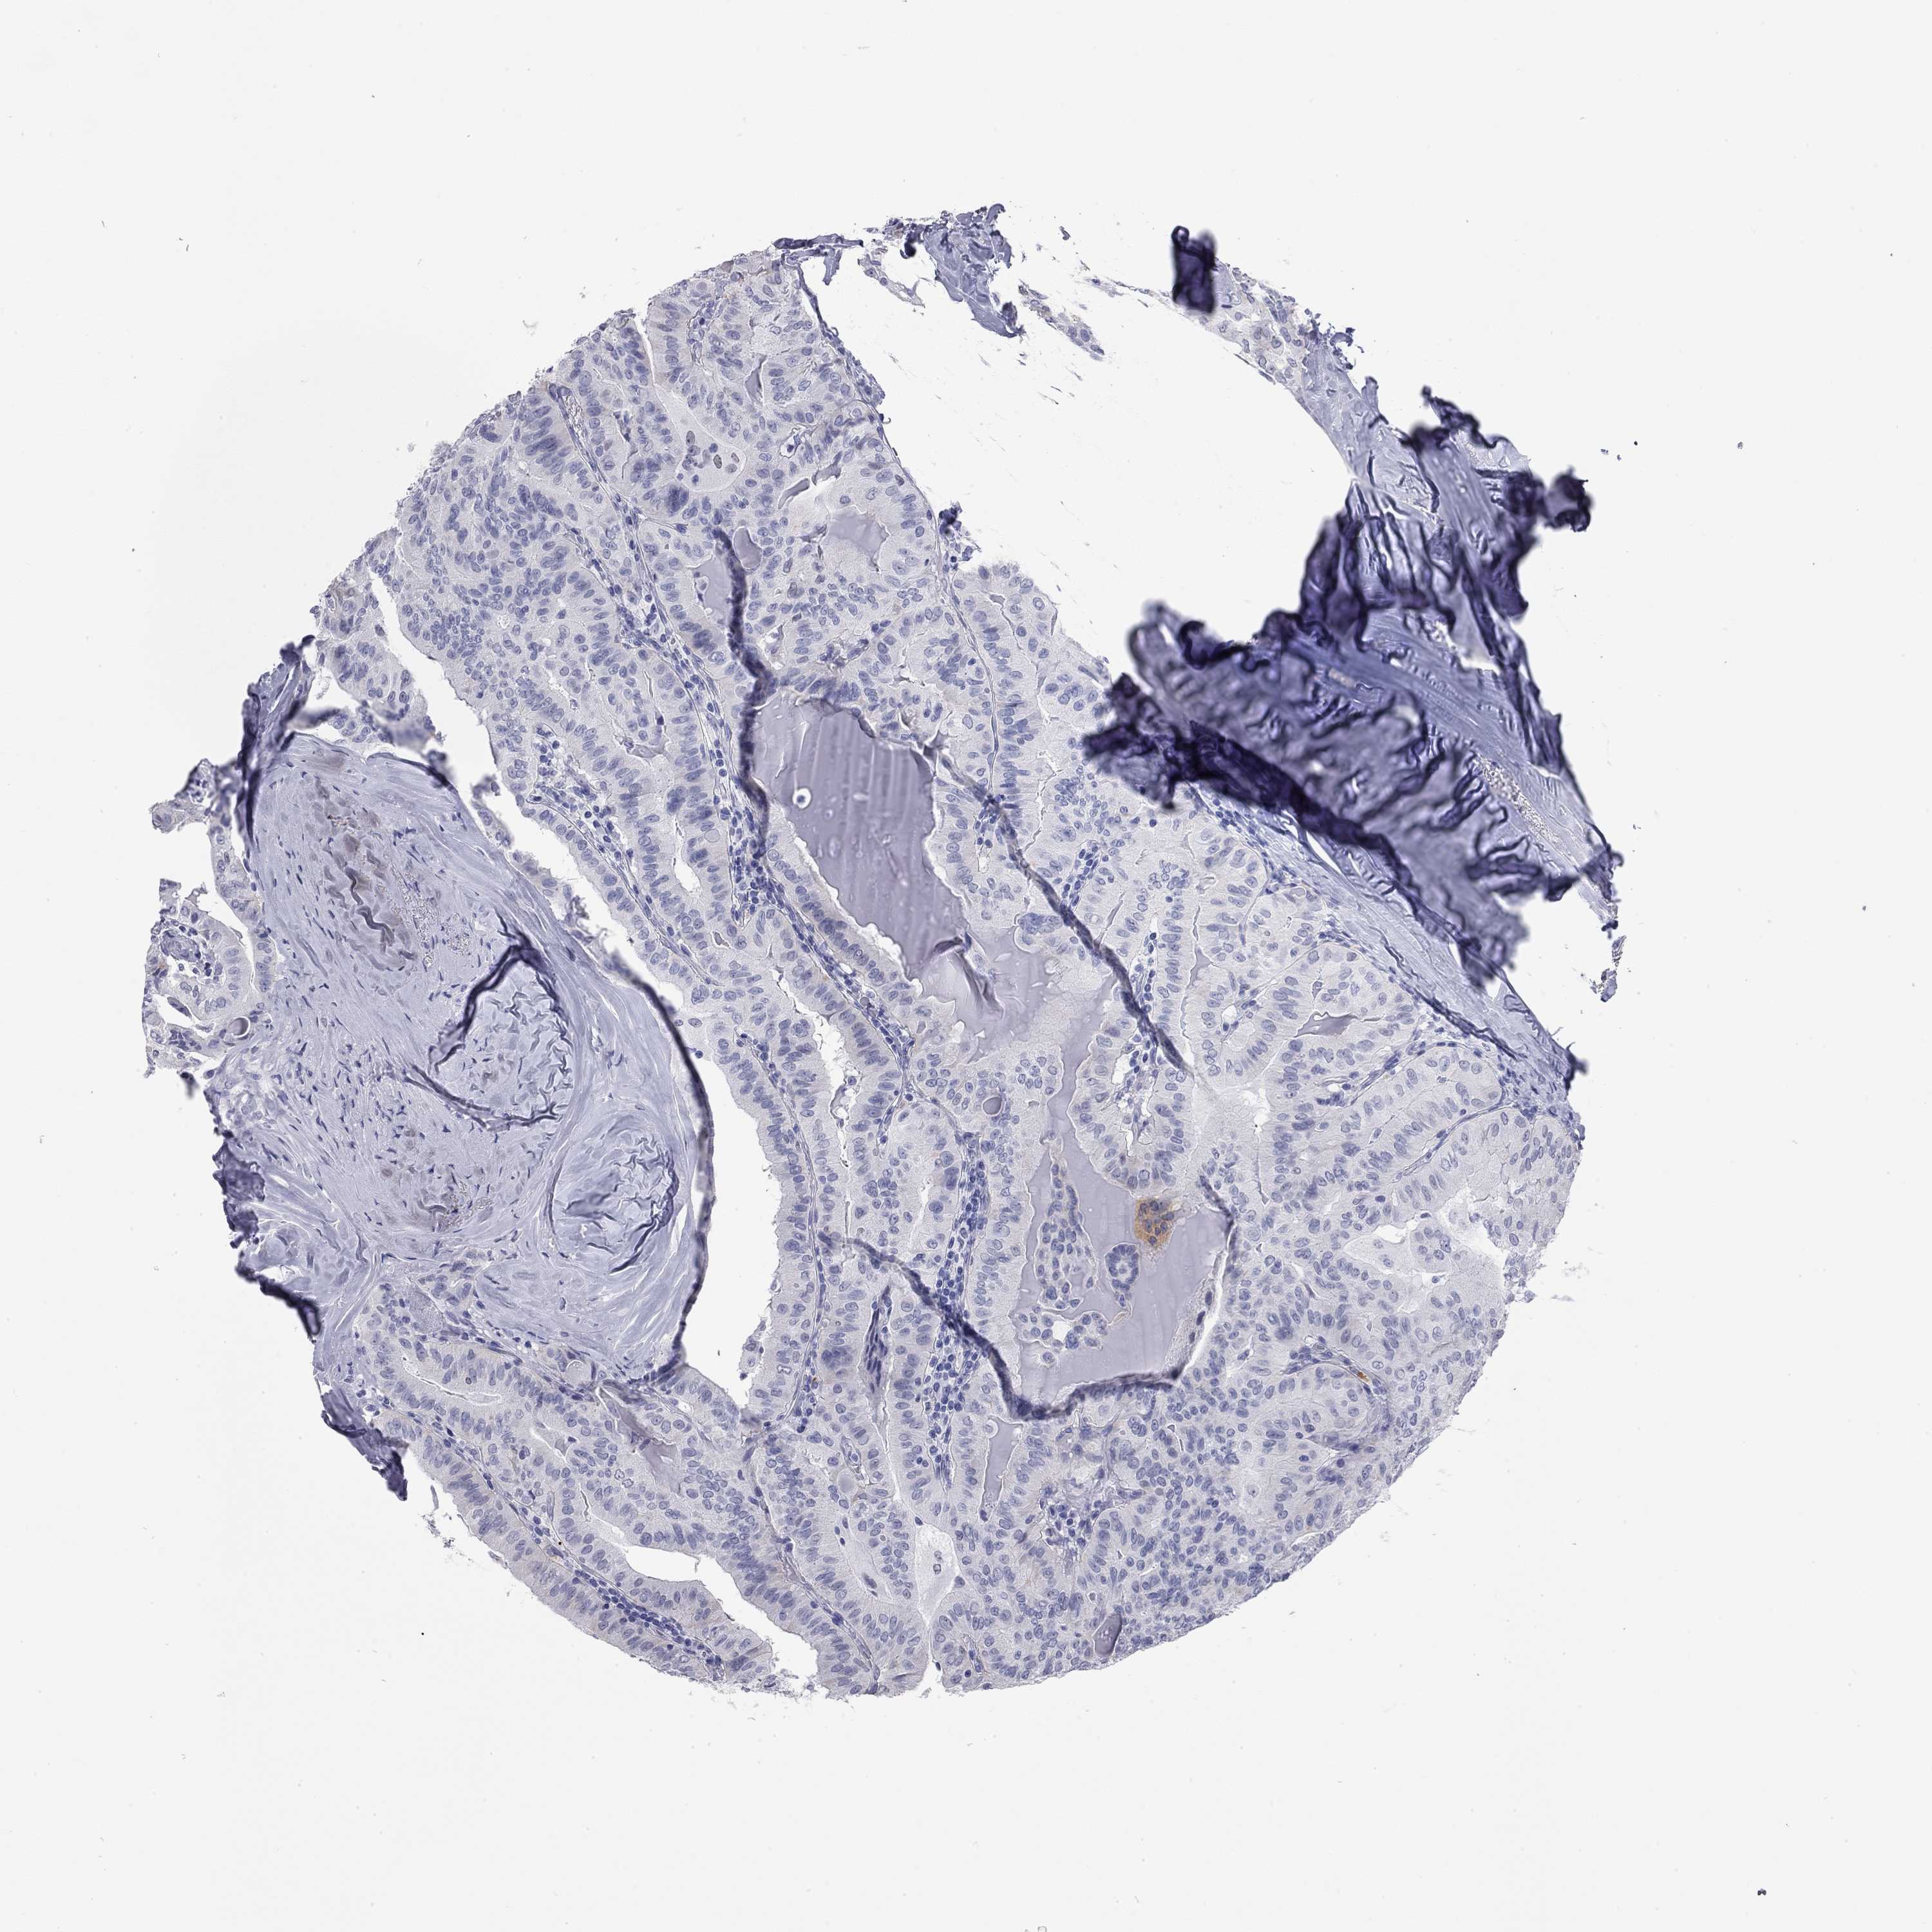

THYROID CANCER - Protein expressioni

A mouse-over function shows sample information and annotation data. Click on an image to view it in a full screen mode. Samples can be filtered based on level of antibody staining by selecting one or several of the following categories: high, medium, low and not detected. The assay and annotation is described here.

Note that samples used for immunohistochemistry by the Human Protein Atlas do not correspond to samples in the TCGA dataset.

Antibody stainingi

Antibody staining in the annotated cell types in the current human tissue is reported as not detected, low, medium, or high, based on conventional immunohistochemistry profiling in selected tissues. This score is based on the combination of the staining intensity and fraction of stained cells.

Each image is clickable and will lead to virtual microscopy that enables deeper exploration of all samples and also displays staining intensity scores, fraction scores and subcellular localization as well as patient and tissue information for each sample.

Antibody HPA021443

Antibody HPA023894

Staining

High

Medium

Low

Not detected

Intensity

Strong

Moderate

Weak

Negative

Quantity

>75%

75%-25%

<25%

None

Location

Nuclear

Cytoplasmic/membranous

Cytoplasmic/membranous,nuclear

Papillary adenocarcinoma, NOS

Follicular adenoma carcinoma, NOS